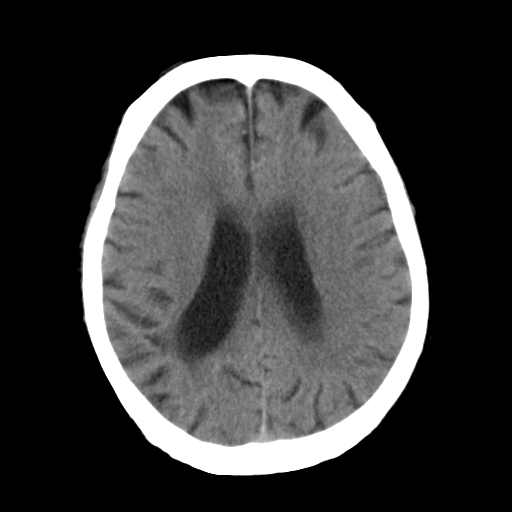

标题: CT25306:男性,75岁。右侧肢体无力一周。 [打印本页]

标题: CT25306:男性,75岁。右侧肢体无力一周。

右侧小脑楔形片状低密度影,考虑脑梗塞,建议mri或增强检查除外肿瘤占位

1)右侧小脑梗塞。2)脑萎缩。